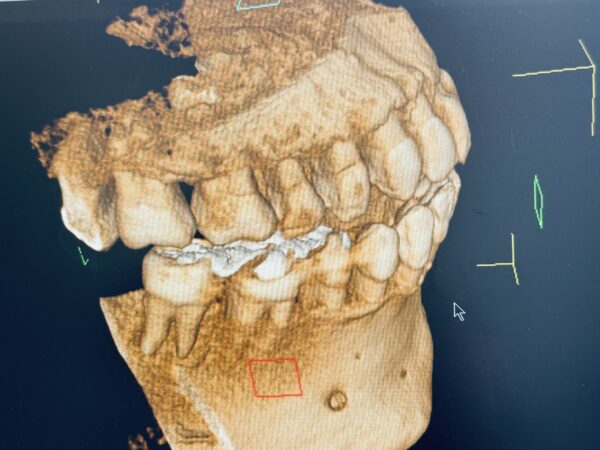

奥歯が歯周病でやられて、骨が溶けてグラグラの状態w

CT画像見て下さい、奥歯の根っこが半分見えてますよねw

コレ、笑い事じゃなくて、ホントに突然来るんです!

私、歯のメンテはかなり気をつけてた方なんです。

3ヶ月に1回、歯医者でクリーニングしてもらっていました。

それがいきなり歯がグラついて「歯周病です」って言われて、治療に入ってる状況。